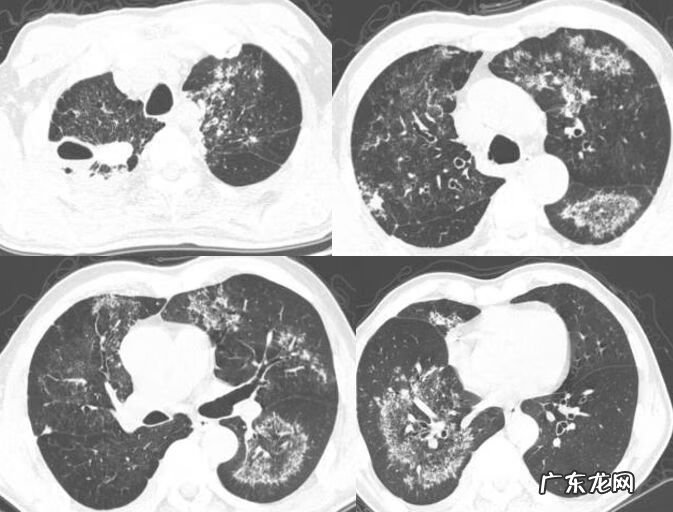

2、典型征象——多发斑片状实变影

这是一位25岁的女性,间断咳嗽,咳痰2月,白色粘痰,沿支气管血管束分布的斑片状实变影(图6),穿刺证实机化性肺炎 。治疗后2个月复查,肺内病变大部分吸收,但是有一部分还未吸收,出现了小叶间隔增厚及牵拉性支气管扩张,这就是非常典型的OP,有点像单纯的肺炎,但还是有所不同,支气管稍微有些扩张,实变影边缘有收缩聚拢 。

双肺下叶沿支气管血管束分布的对称实变影,其内可见明显的牵拉性支气管扩张(图7),最典型影像特征及典型分布OP 。